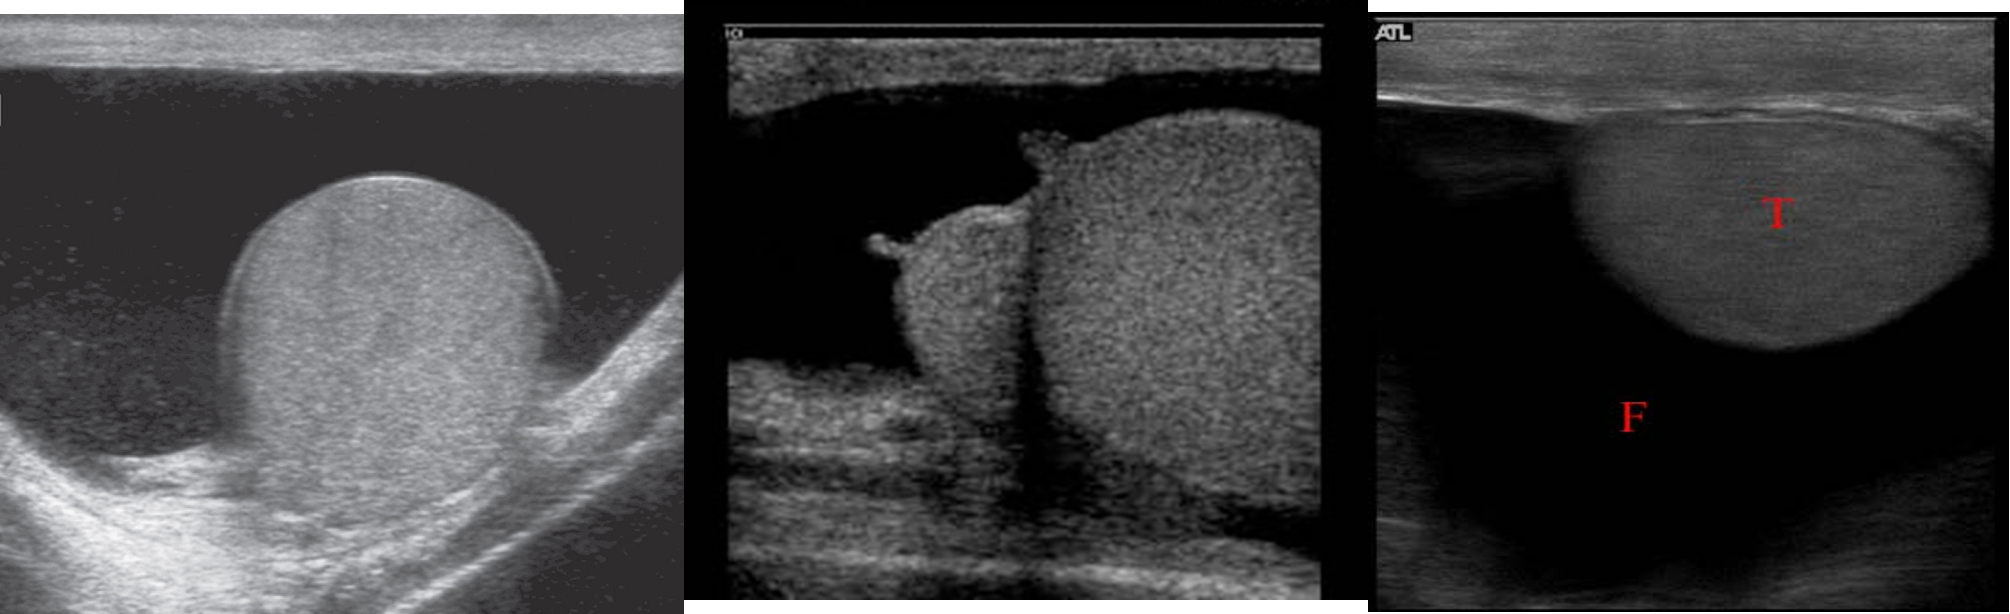

Simple Hydrocele

A hydrocoele is demonstrated surrounding an otherwise normal testis .